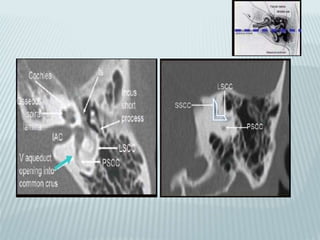

COCHLEA

 More than 2.5 turns

 Basal and intermediate spirals readily seen

 Basal turn opens post into round window

 Cochlea encircles central osseus axis of

modiolus

SEMI CIRCULAR CANALS

 Project off superior,posterior and lateral

aspects of vestibule

 Upper margin of superior SCC forms

superior convexity on petrous pyramidal

roof(Arcuate eminence)

 Posterior SCC points

posteriorly along

petrous ridge

 Lateral SCC juts

lateraly into

epitympanum

(cholesteatoma here

erodes lateral

cortex:fistulization)